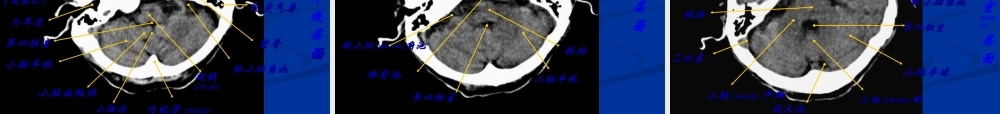

头颅头颅(tóulú)(tóulú)CTCT读片读片阜阳市人阜阳市人民民(rénmín(rénmín))医院医院CTCT、、MRMR室室屠文刚屠文刚第一页,共一百零二页。CT的发展史CT是英国的电气工程师Hounsfield于1969年设计成功。1972应用于临床。CT的诞生开创了数字化影像的先河,是放射学领域的重大突破,极大地促进了医学影像学的发展。因为CT的发明,对医学影像学的重要贡献(gòngxiàn),Hounsfield于1979年获得诺贝尔生理或医学奖。第二页,共一百零二页。CT成像的基本原理CT是根据人体的正常组织结构对x光线吸收能力的不同,利用旋转发射的x线对人体的各部位进行(jìnxíng)一定厚度的断层扫描,由探测器接受穿过该层面衰减的x线。x线→可见光→电信号→模拟/数字转换器→可供计算机处理的数字(像素)→数字化图像。第三页,共一百零二页。CT的组成CT主要三部分组成1.扫描部分(x线球管探测器扫描机架)该部分用于完成对检查部位的扫描。2.计算机系统将扫描收集的大量数据进行(jìnxíng)存储、运算。3.图像显示、打印和存储系统。第四页,共一百零二页。常规检查,由于CT的密度分辨率高,对软组织的显示优于常规X线检查。增强CT扫描检查,除能分辨血管的解剖结构外,还能观察血管与病灶之间关系,病灶部位的血供情况和血液动力学的变化。因为轻微活动会造成伪影,使图像难以诊断,除取得患者合作外,对难于合作的患者或儿童需给予(jǐyǔ)镇静剂或麻醉。第五页,共一百零二页。(sǎomiáo)扫描基线1.听眉线:外眶上嵴到耳屏上缘2.听眦线:外眼眦到外耳道中心3.听眶线:外眶下嵴到耳屏下缘颅脑扫描一般以听眦线为基线向上(xiàngshàng)扫至头顶层厚:8-10mm,层距:10mm第六页,共一百零二页。Reid基线(RBL):为眶下缘至外耳道中点(zhōndiǎn)ɡ的连线,为头部断层标本制作的常用基线。外耳道眶上缘眶下缘•听眦线第七页,共一百零二页。1.冠状面2.矢状面3.横断面第八页,共一百零二页。常规扫描一般情况下不用高分辨率扫描,常规扫描层厚与层距:10mm,扫描方式采用连续扫描。特殊扫描薄层扫描:层厚5mm以下,用于观察细小病灶,扫描患者(huànzhě)的射线剂量增加。重叠扫描:在连续扫描方式下,层距小于层厚,减少部分容积效应,不会漏诊小病灶。第九页,共一百零二页。原则上增强扫描是在平扫后针对病变进行的扫描,出现下列情况一般应考虑增强扫描:平扫后发现某些征象(zhēngxiàng)如组织密度异常、有占位性怀疑...